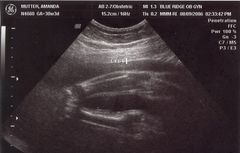

August 8, 2006: Another Ultrasound

Little did my parents know I'd be making my entrance in less than a month. The OB didn't suspect either :-)

My face is recognizable already.